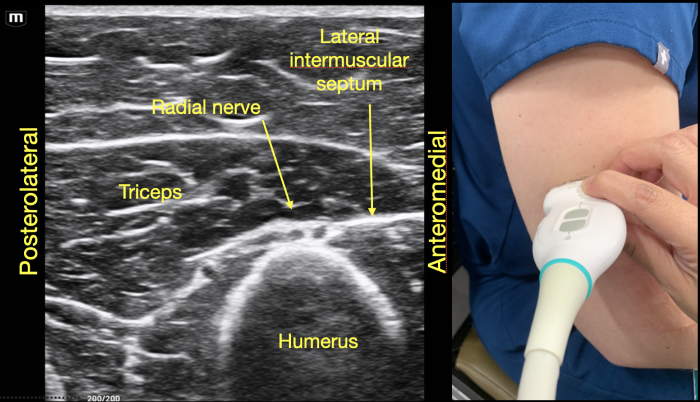

As the probe is moved distally along the spiral groove, the posterior cutaneous nerve of the forearm can be seen branching from the radial nerve just prior to the lateral intermuscular septum (Figure 7D). In Video Clip 1, the radial nerve passes from the triceps into the biceps through the linear echogenic lateral intermuscular septum, which is a hyperechoic connective tissue layer separating the dorsal and anterior compartment of the arm.13

RadialNerve-Image6 Aug2024.pngFigure 6. Radial nerve joins the posterior cutaneous branch of the forearm proximal to the lateral intermuscular septum in the dorsal compartment of the arm.